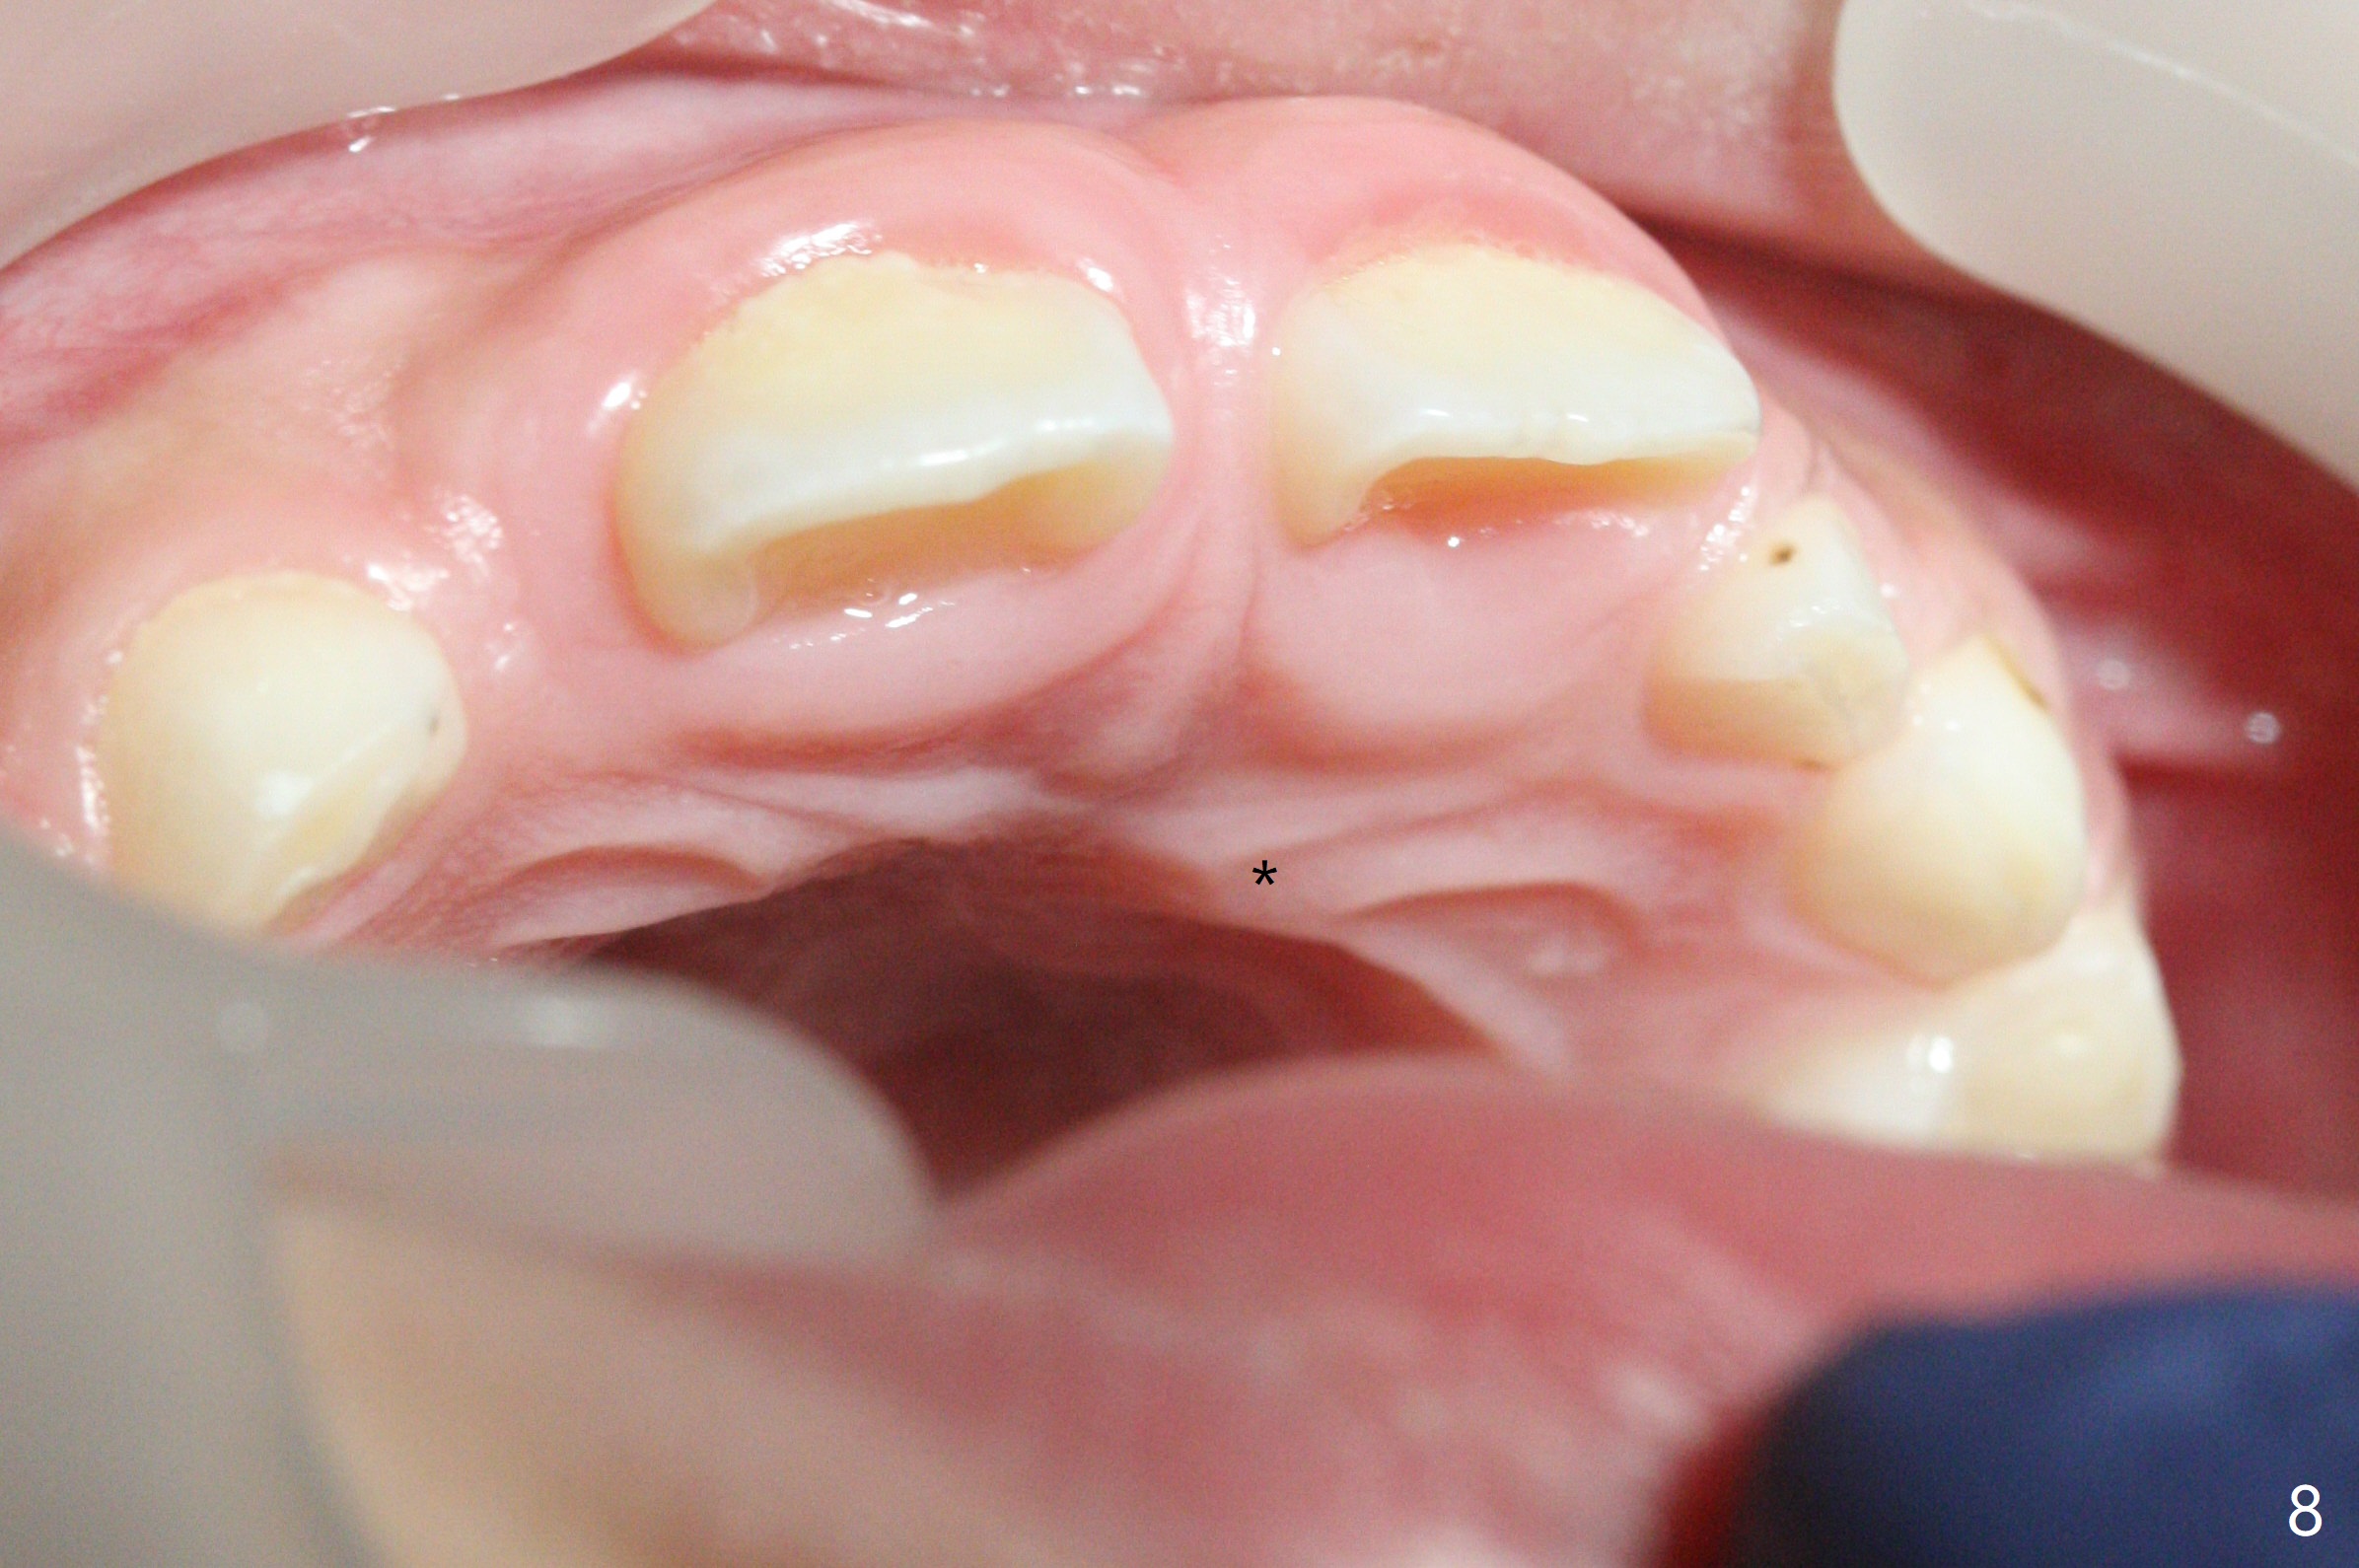

There is a large diastema between the upper central incisors (Fig.7). The left anterior palate is slightly elevated (Fig.8 *). In fact the cortex overlying the mesiodens (Fig. 9 *, 11 <) is to be removed with a surgical handpiece in order to extract the mesiodens (Fig.10). The left central shifts mesial in 7.5 months postop, whereas the right one remains in place (Fig.12). The tooth #7 is unerupted 1 year 4 months postop (Fig.13).